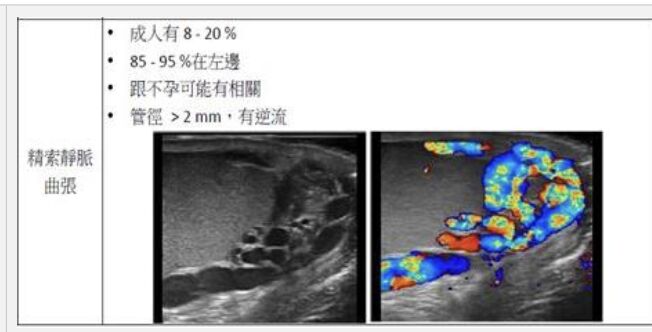

64.下圖為陰囊的超音波影像,最有可能的診斷為:

(D)精索靜脈曲張(varicocele)